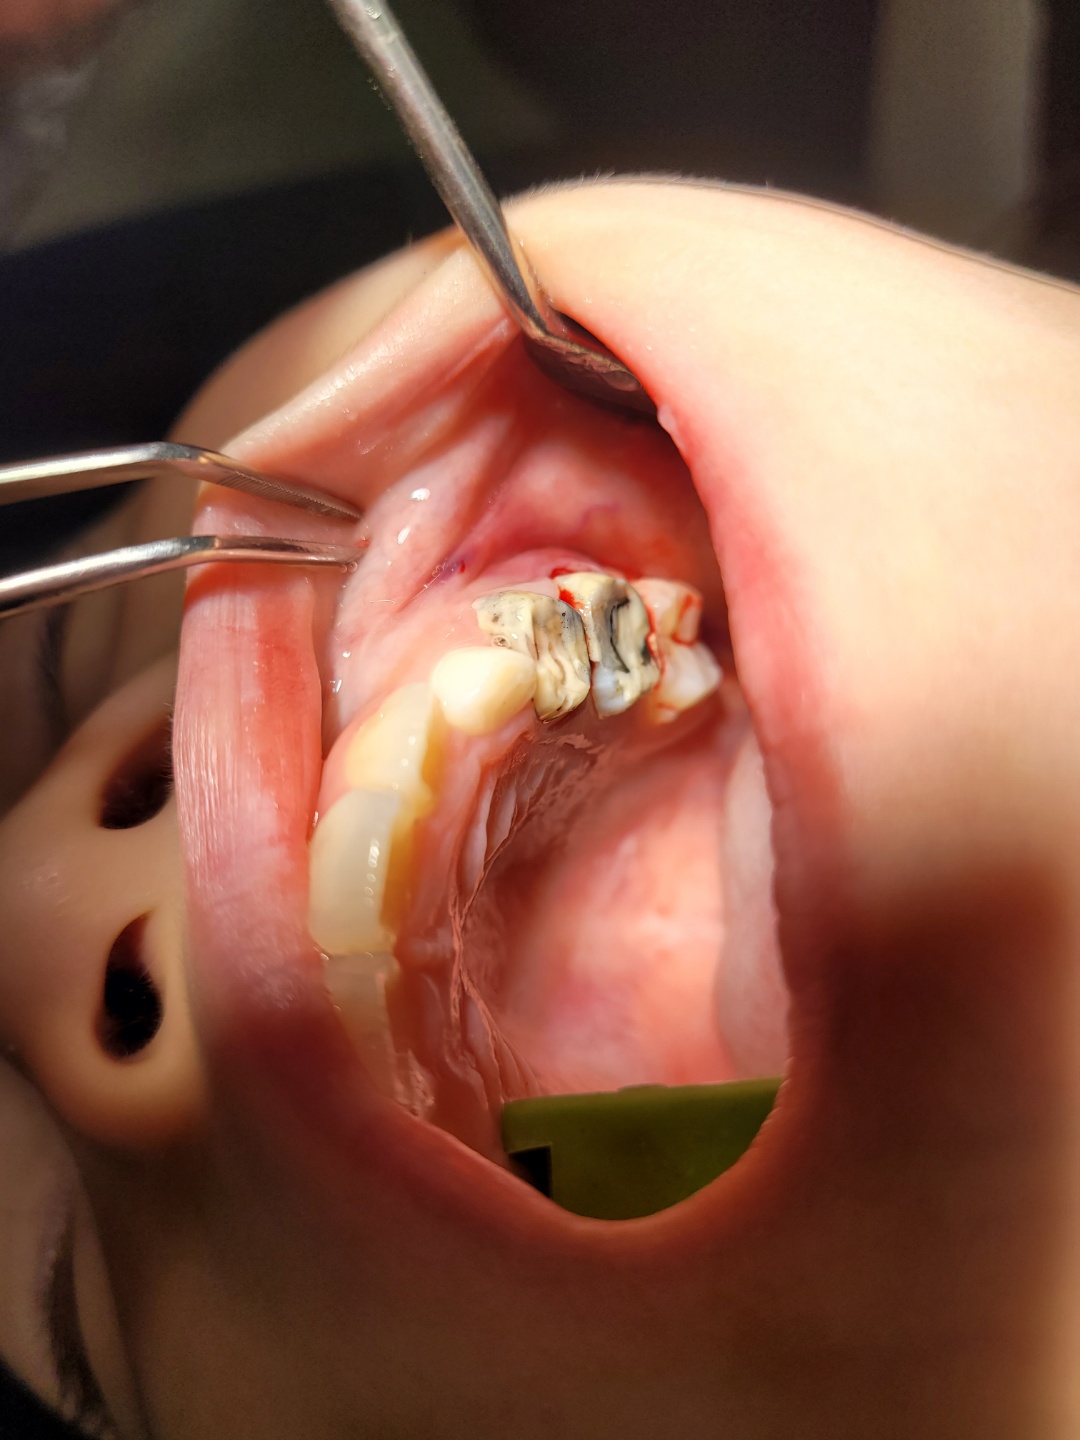

그리고 왼쪽 벗겨진 크라운 옆에 것도 흔들리는데 염증까지 있어서 염증을 짜내고 그 쪽도 크라운을 다시 해야할 것 같다고 하셨습니다. 총 크라운 2개를 다시 ㅠ.ㅠ

■ 초등학생 어금니 크라운 과정

1) 먼저 사진을 찍고 국소마취를 합니다. 마취 주사를 맞을 때 달달달 떠는 발을 보니 얼마나 불쌍하던지 ㅠ.ㅠ

3) 크라운을 씌우기 위해 어금니를 다듬어요. 지잉지잉~~~~ 불쌍한 것 ㅠ.ㅠ

염증이 있어서 염증도 많이 짜냈답니다. 꽤깊게 바늘같은 거루 찔러서 ㅠ.ㅠ 고름 보여주셨어요.

소심한 블로거가 사진을 찍어도 될까요? 했더니 쿨하게 찍으셔도 됩니다 했던 의사쌤 감사합니다. ^^

4) 사이즈에 맞춰서 크라운을 끼워봅니다.

이렇게 사이즈별로 나와있는 크라운을 하나씩 하나씩 ○○이에게 맞춰서 끼워보셨어요. 왼쪽 사진에 위쪽 어금니 2개에 크라운을 꼽고 괜찮은지 씹어보고 하는 과정을 여러번 하셨습니다.

5) 맞는 사이즈를 찾으면 치과용 접착제로 부착하여 마무리 합니다.